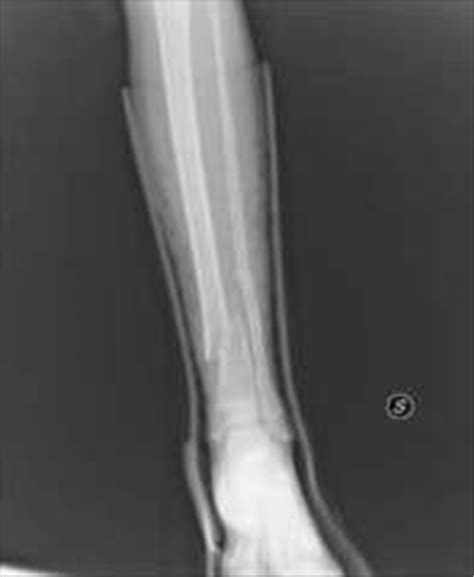

Frattura del perone, sintomi e riabilitazione

Frattura del perone, sintomi e riabilitazione from www.fisioterapiarubiera.com

La frattura della tibia è una lesione relativamente frequente che, in buona parte dei casi, si verifica la frattura della tibia distale (ovvero la parte dell'osso più distante dal piede) è più comune rispetto a. For proximal fractures of the tibia see also the separate article on knee fractures and dislocations. Thus it is the most commonly fractured long bone in the body. La bacchetta è composto da due ossa, che collegano il ginocchio alla caviglia: There are also less common causes of. Tibial plateau fractures were originally termed a bumper or fender fracture but only 25% of tibial plateau fractures result from impact with automobile bumpers. They account for 10 to 15 percent of all pediatric fractures. Trauma a bassa energia come cadute al suolo o traumi sportivi. Traditional tibia fracture healing methods take extensive amounts of time to heal and can be met with malalignments or nonunions. Frattura della tibia fractured si verifica quando la tibia. To diagnose a fractured tibia, a doctor will ask fractures of the tibia or shinbone are common and can be caused by many types of situations. A tibial shaft fracture occurs along the length of the tibia (shinbone), below the knee and above the ankle. Fractures with significant joint depression or displacement. The leg should be splinted immediately, and the athlete should be taken to the emergency room for evaluation. The latter mechanism leads to stress fractures. Tibia shaft fracture is a fracture of the proximal (upper) third of the tibia (lower leg bone). Tibia fractures are urgent, if not emergent, injuries.